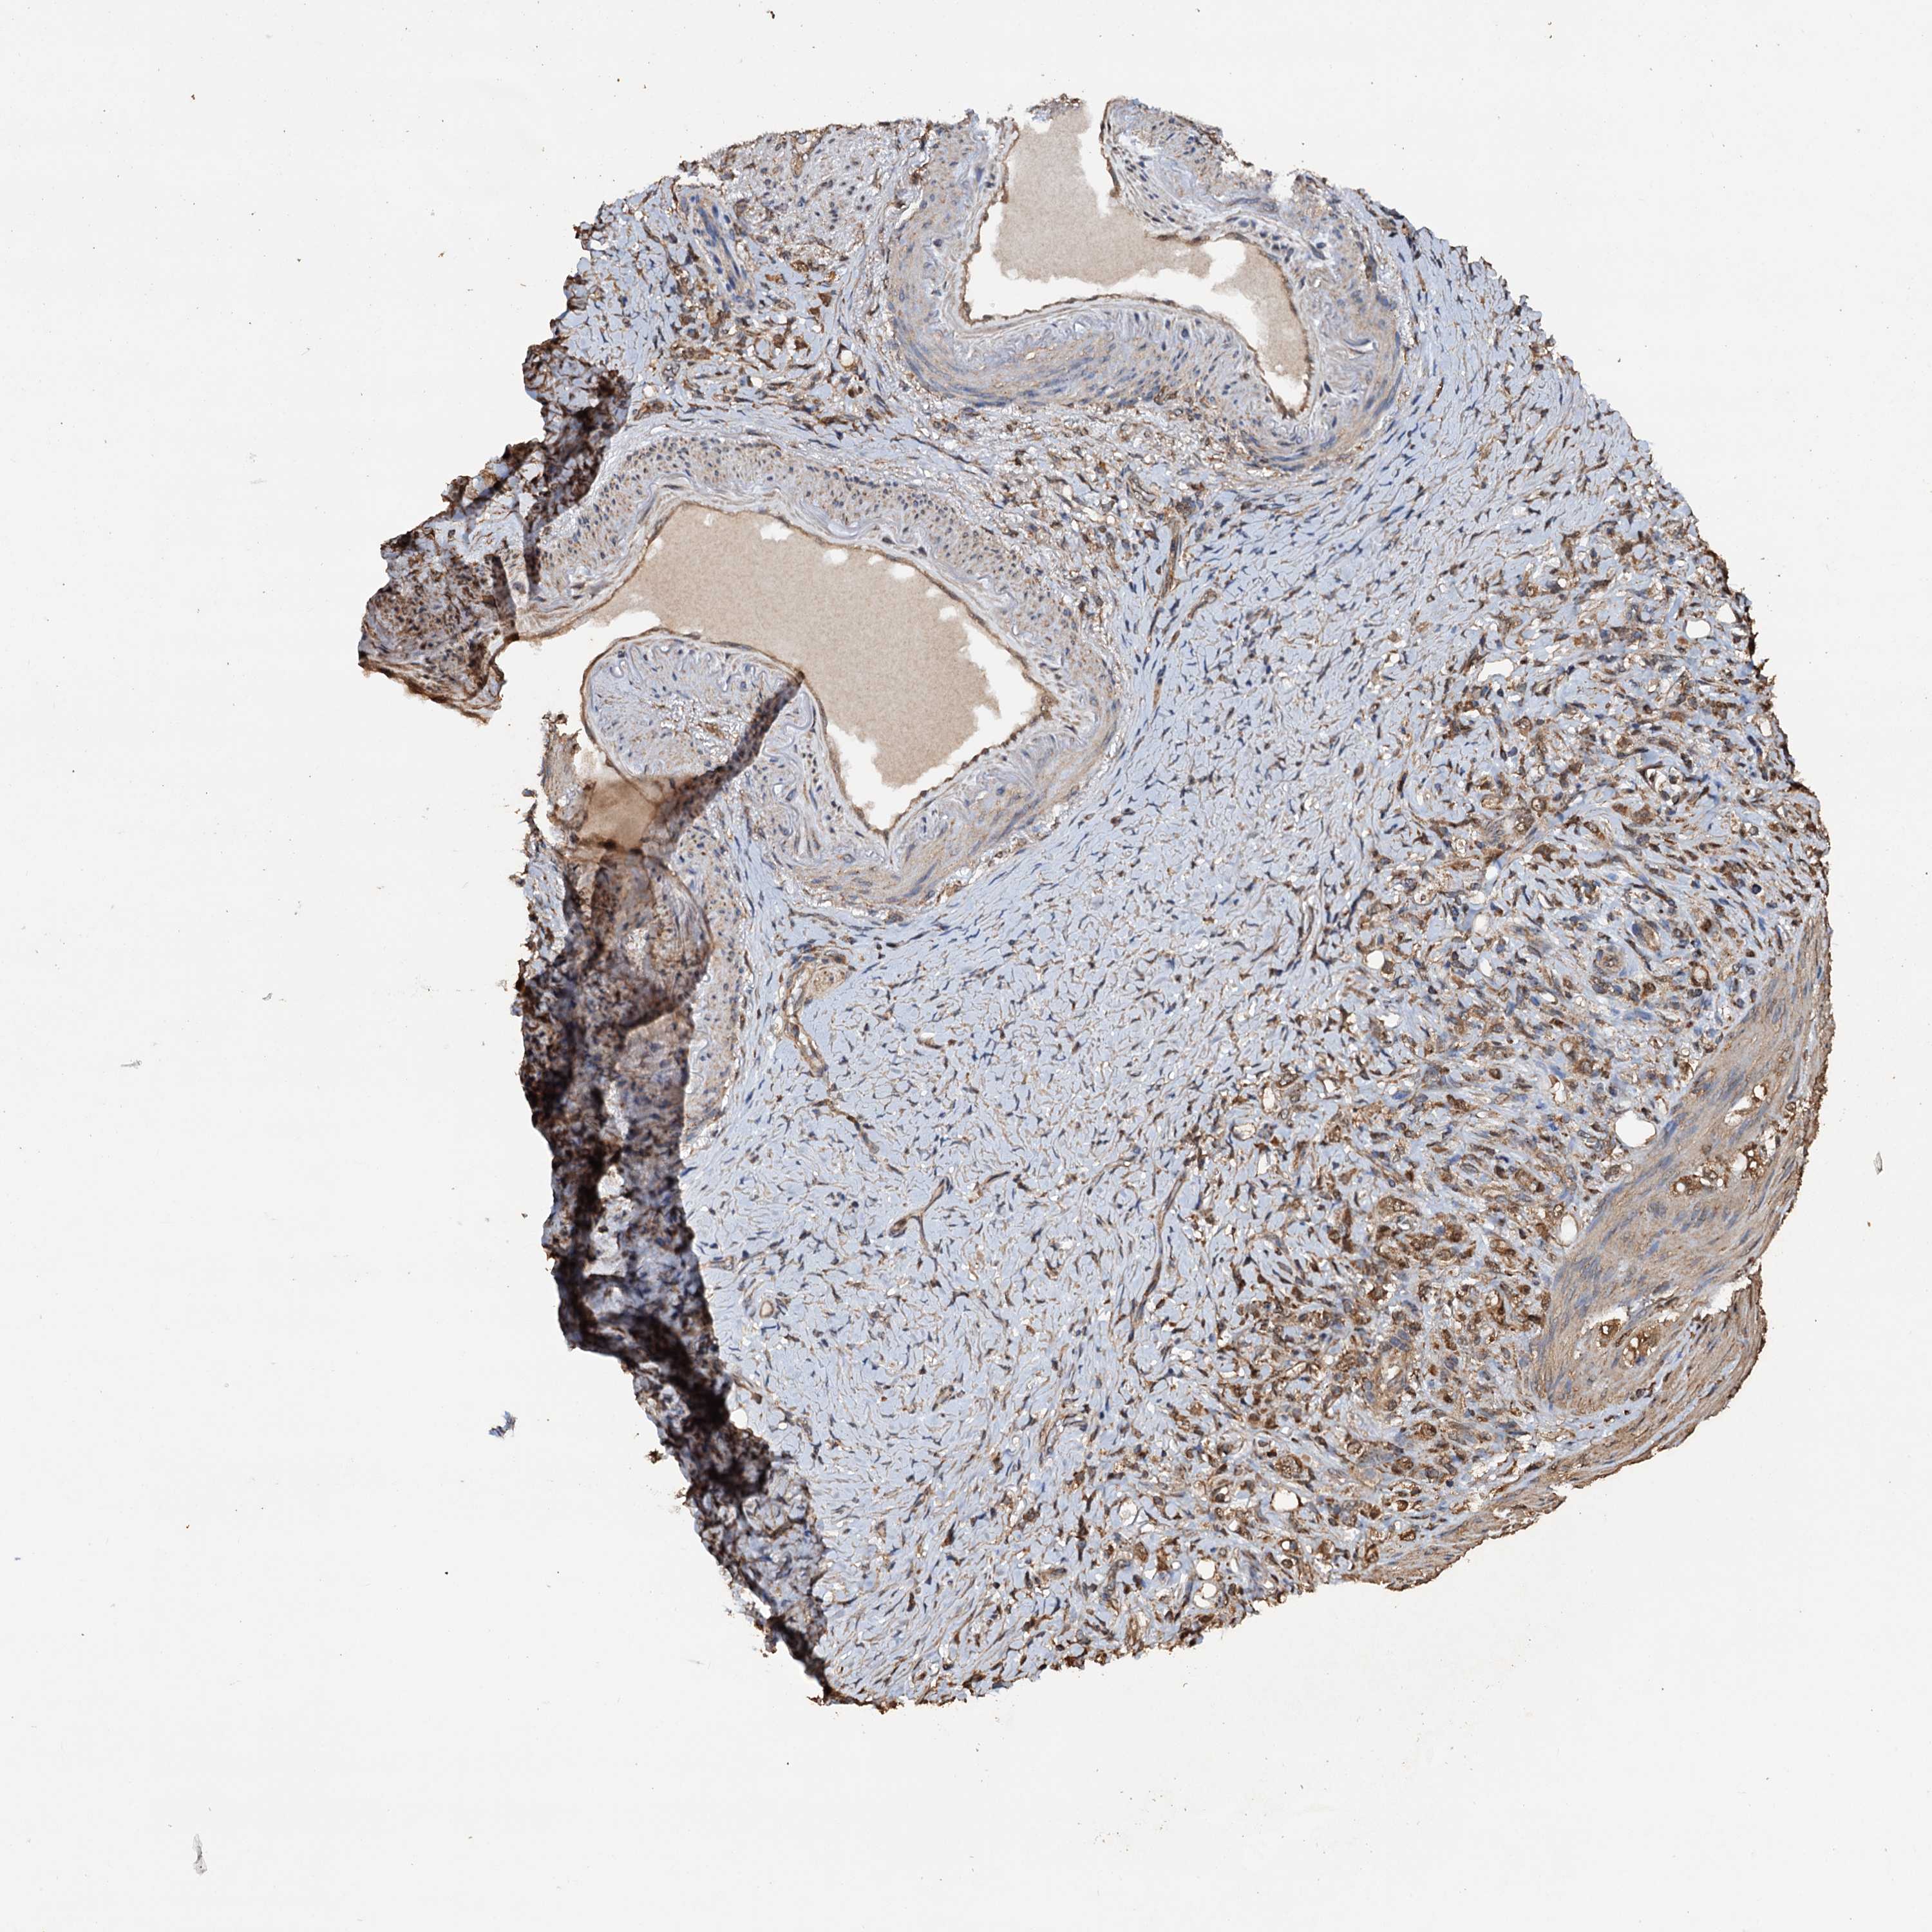

STOMACH CANCER - Protein expressioni

A mouse-over function shows sample information and annotation data. Click on an image to view it in a full screen mode. Samples can be filtered based on level of antibody staining by selecting one or several of the following categories: high, medium, low and not detected. The assay and annotation is described here.

Note that samples used for immunohistochemistry by the Human Protein Atlas do not correspond to samples in the TCGA dataset.

Antibody stainingi

Antibody staining in the annotated cell types in the current human tissue is reported as not detected, low, medium, or high, based on conventional immunohistochemistry profiling in selected tissues. This score is based on the combination of the staining intensity and fraction of stained cells.

Each image is clickable and will lead to virtual microscopy that enables deeper exploration of all samples and also displays staining intensity scores, fraction scores and subcellular localization as well as patient and tissue information for each sample.

Antibody HPA040512

Antibody HPA044220

Staining

High

Medium

Low

Not detected

Intensity

Strong

Moderate

Weak

Negative

Quantity

>75%

75%-25%

<25%

None

Location

Nuclear

Cytoplasmic/membranous

Cytoplasmic/membranous,nuclear

Adenocarcinoma, NOS

Adenocarcinoma, High grade